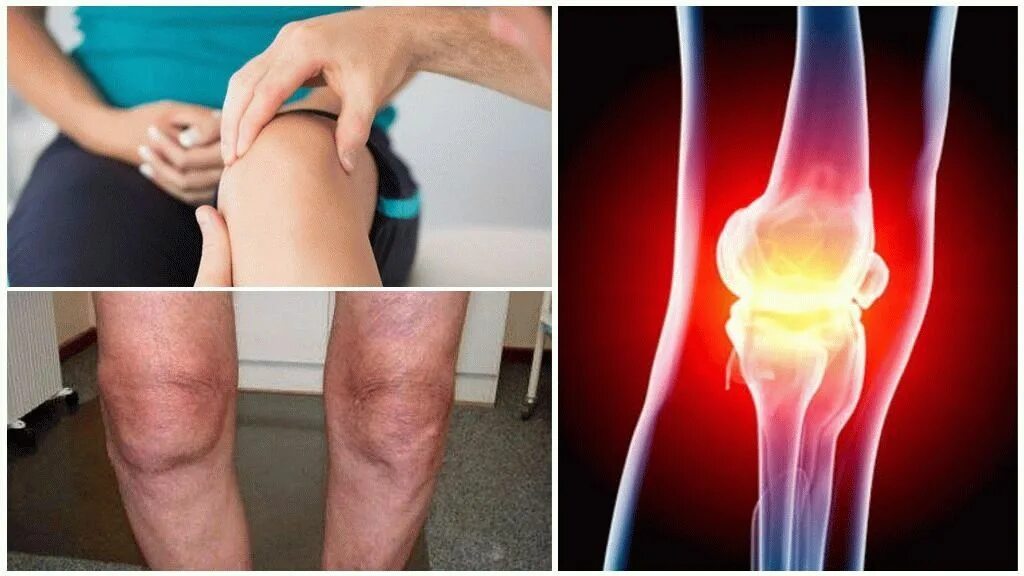

Явления остеоартроза